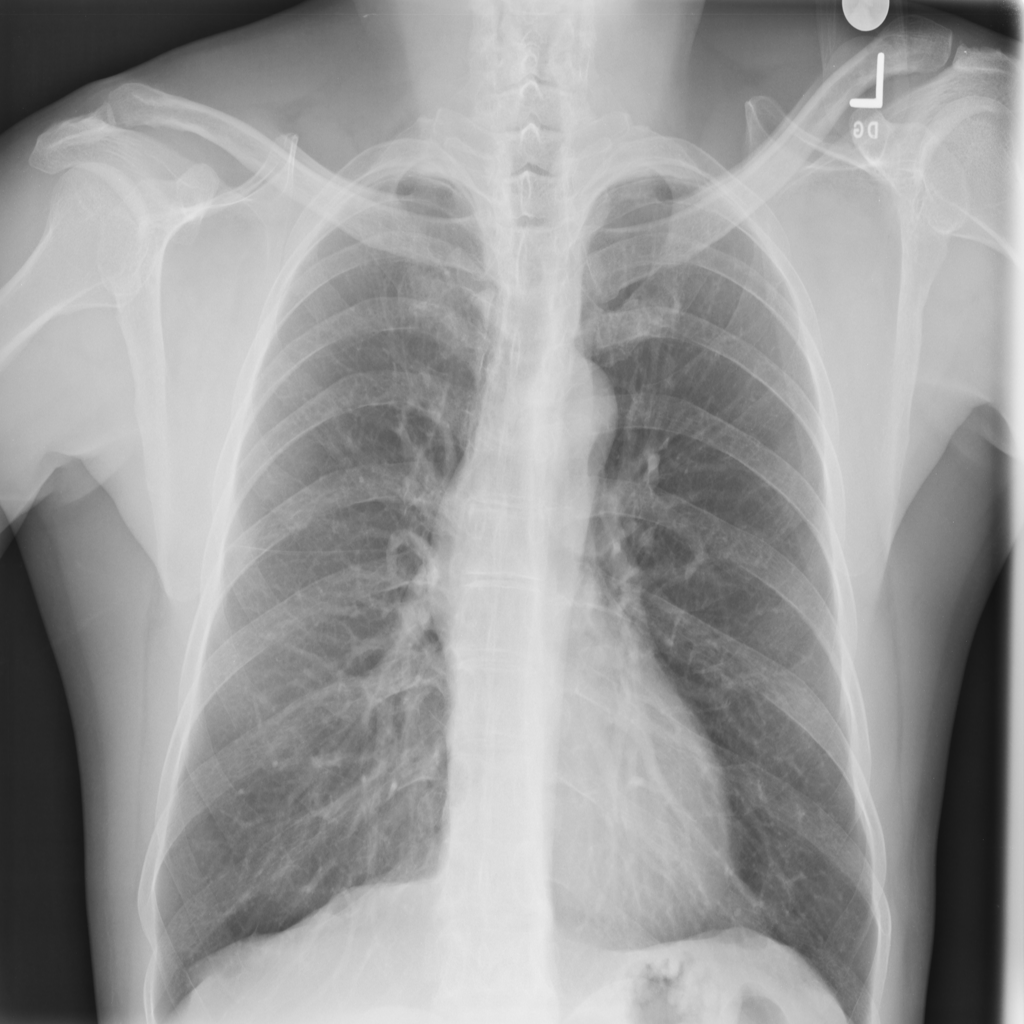

PAT-B0DB · IMG-003Emphysema

PAT-B0DB · IMG-003

PA